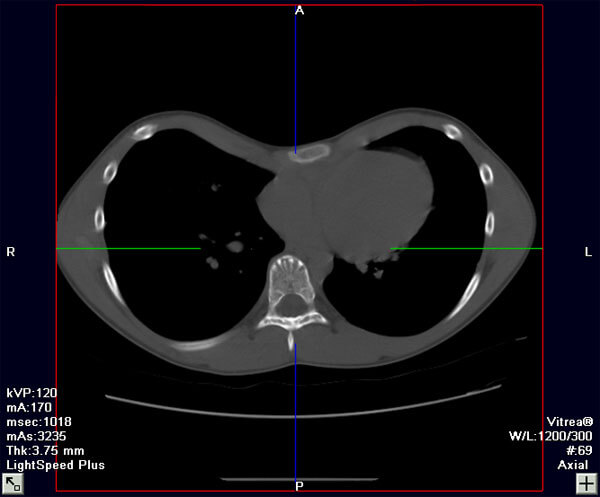

The following are photos and CT images from before and after repair of pectus excavatum.

CT Image (Axial View), Before Repair

CT Image (Axial View), After Repair